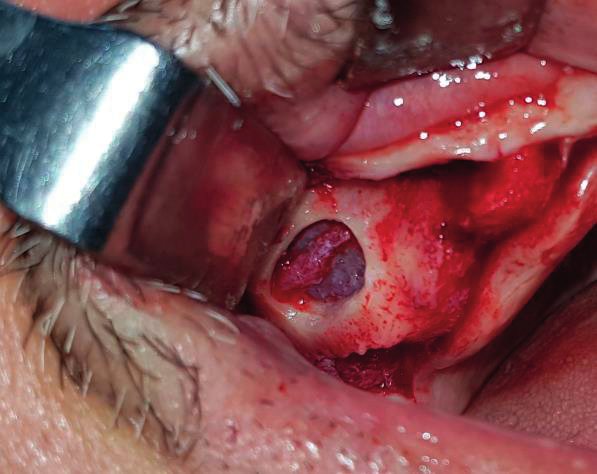

A. Ανύψωση κρημνού Ο κρημνός πρέπει να ανυψωθεί ελάχιστα, ώστε να ανοίξει ολόκληρη η περιοχή τοποθέτησης του μοσχεύματος. Προετοιμάστε το έλλειμμα για τοποθέτηση του μοσχεύματος.

B. Εφαρμογή της BIONGRAFT Πάστας Ενέστε τη BIONGRAFT Πάστα και πιέστε απαλά για 5 δευτερόλεπτα, ώστε να πάρει το σχήμα του ελλείμματος, χρησιμοποιώντας στείρα και ξηρά γάζα.

Γ. Κλείσιμο κρημνού Επανατοποθετήστε τον κρημνό και ράψτε για μέγιστο κλείσιμο.